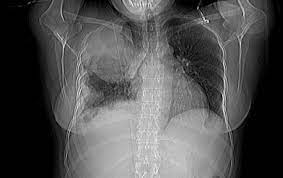

Year Old Man With Sarcomatoid Malignant Pleural Mesothelioma A Download Scientific Diagram

Year Old Man With Sarcomatoid Malignant Pleural Mesothelioma A Download Scientific Diagram from www.researchgate.net